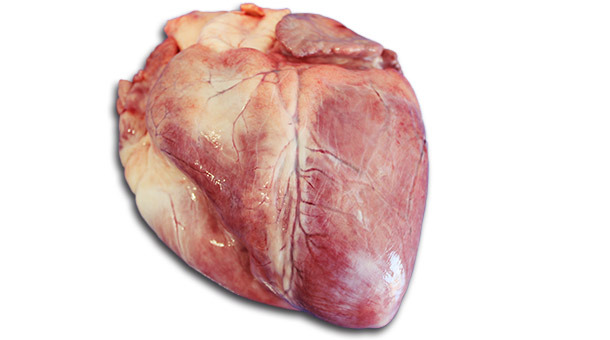

Les deux cadavres présentaient une bonne condition corporelle et de la cyanose prononcée sur la zone ventrale de l’abdomen et le cou. Les muscles squelettiques, particulièrement le M longissimus dorsi et le M semimembranosus, ont montré des zones pâles, peu flexibles et friables (figure 1). Le myocarde des deux truies avait aussi des altérations blanchâtres localisées (figure 2). De plus, il y avait des pétéchies subépicardiques multifocales. Sur l’une des truies on a aussi observé une pleurésie fibrineuse locale légère ainsi que des nodules nécrotiques totalement encapsulés dans les deux lobes diaphragmatiques du poumon. L’estomac des deux truies contenait de l’aliment sec. On n’a pas trouvé de lésions pathologiques dans la cavité abdominale, dans les intestins, le foie, la rate, les reins, la vessie, le cerveau ni les os.

Figure 1: Pâleur prononcée du M. semimembranosus

A partir des découvertes macroscopiques, en particulier les altérations du muscle squelettique, on a suspecté qu’il s’agissait d’un cas de déficience en vitamine E/Sélénium. Pour cette raison, on a fixé des échantillons de M longissimus dorsi et de M semimembranosus, dans du formol et on les a envoyés au laboratoire (Lab 1) pour un examen histopathologique. Les nodules nécrotiques encapsulés observés dans les deux lobes diaphragmatiques d’une des truies étaient typiques d’une infection chronique par Actinobacillus pleuropneumoniae qui probablement n'était pas la cause de la mort. Cependant, on a prélevé deux échantillons de tissu pulmonaire (altéré et non altéré) et un écouvillon de l’épithélium bronchique pour leur analyse bactériologique.

Dans le second examen histologique des échantillons de muscle squelettique, les chercheurs de l’institut vétérinaire pathologique et légal ont observé des altérations dans les cellules musculaires isolées qui présentaient différentes étapes de dégénérescence des fibres musculaires. Certaines étaient gonflées et présentaient une perte de striation. D’autres parties des muscles montraient des signes de nécrose aigue des fibres musculaires (figure 3). Les observations microscopiques du myocarde coïncidaient avec un trouble cardiaque aigu. Ces résultats ont confirmé les découvertes macroscopiques caractérisées par la pâleur des muscles et des fibres peu flexibles et friables qui ont levé les suspicions de dégénérescence musculaire nutritionnelle principalement due à un manque de vitamine E/Sélénium.